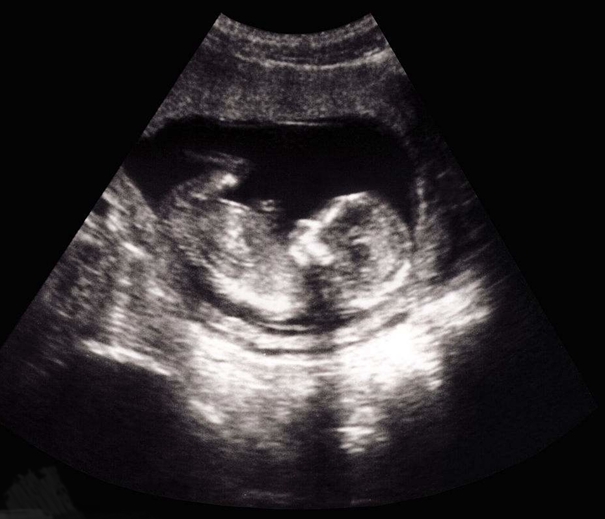

超声医学由于采用了灰阶显示、实时扫描与动态聚焦等手段,因而声像图的质量显著提高,直观、逼真、清晰而富有层次。对人体心、肝、胆、肾、颅脑、眼球、子宫、乳房及盆腔等,都有很好的诊断价值。应用这种声像图,不仅能显示脏器的外形,而且能深入观察其内部结构。还能定位指导穿刺。从妊娠5周到分娩前胎儿的生长发育过程都能从影像图中显示出来,这对于计划生育、检查胎儿畸形、鉴别性别,都很有意义。诊断时射入人体的超声能量很小,一般为10mW/cm2左右,无致伤作用。已成为一种常规检查法。将电子计算机技术引入超声诊断,产生了超声CT技术。它将获取超声通过脏器的传播时间及幅度或衰减随频率的变化数据,输入电子计算机里,经过信号数字处理和综合后再给出组织的切面图像,这种技术的特点是能得到活体组织内部超声参量的空间分布。对于1MHz的超声,切面图像的分辨力可到5mm。目前已到临床试验阶段。